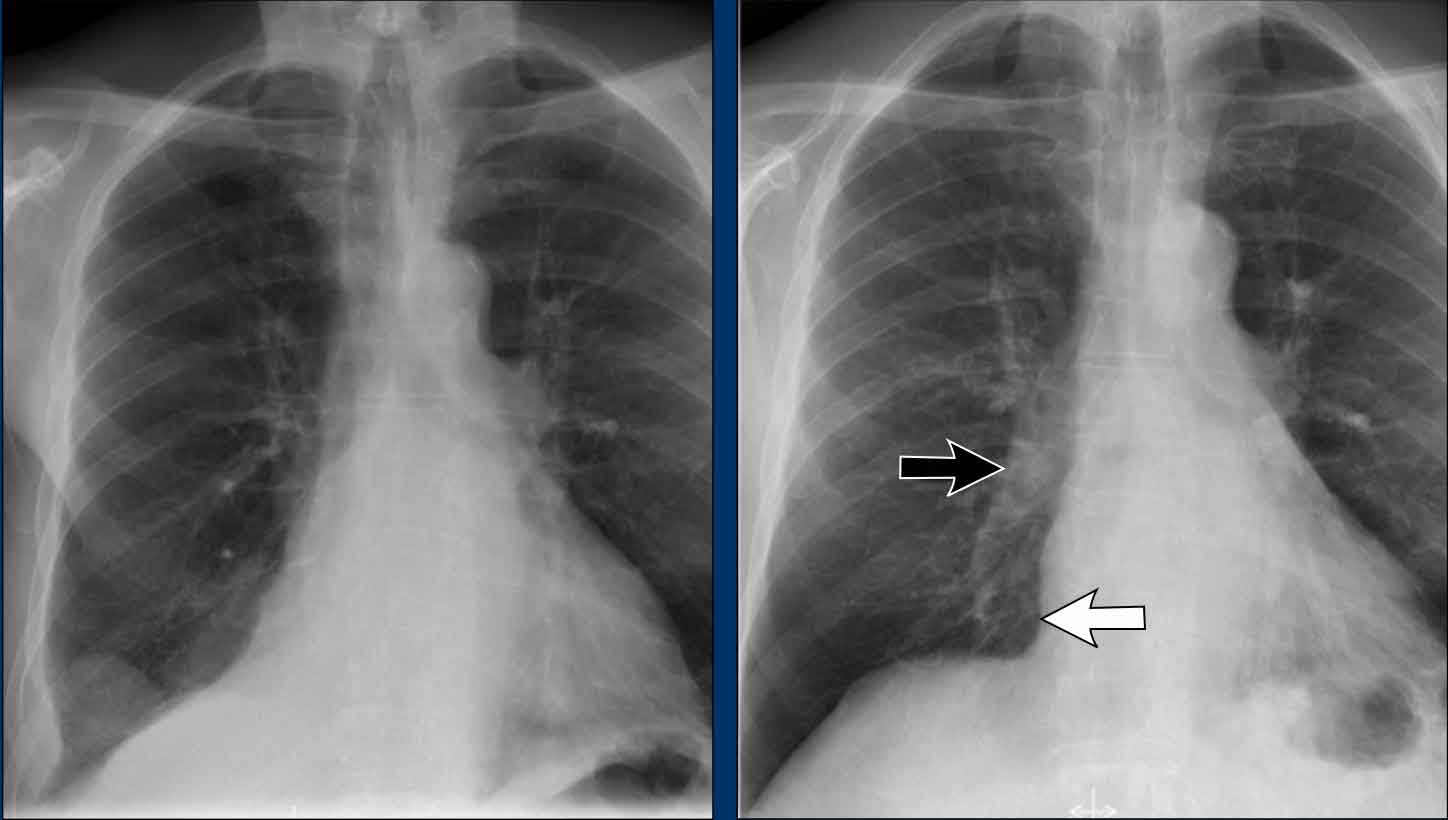

Case Example: Subtle Signs of Congestive Heart Failure

Begin by reviewing these current chest radiographs.

Based solely on these images, one might suspect congestive heart failure (CHF), though the findings are subtle.

Now review the previous study…

Scrolling between the current and prior films significantly increases diagnostic confidence in your diagnosis of congestive heart failure.

Key comparative findings include:

- Cardiac size: Slightly increased compared to the previous study; however, cardiomegaly was already present.

- Pulmonary vasculature: Mild vascular engorgement suggesting elevated pulmonary venous pressure.

- Interstitial markings: Subtle signs of interstitial edema .

- Pleural effusions: Bilateral small effusions, with subtle changes in the inferoposterior borders of the lower lobes, suggesting fluid accumulation.